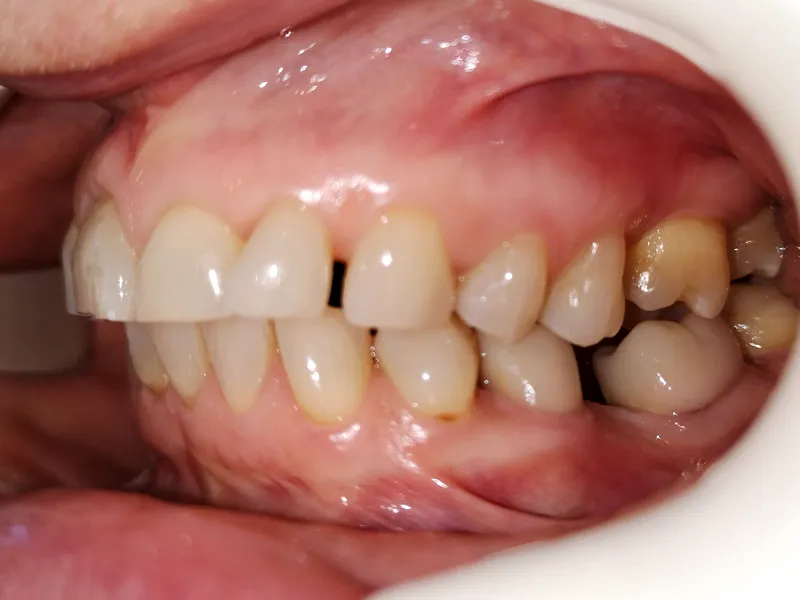

În multe cazuri, ortodonția devine o etapă foarte importantă în tratamentele dentare complexe.

Când dinții nu mai stau la locul lor: de ce uneori ortodonția e esențială înainte de o lucrare dentară